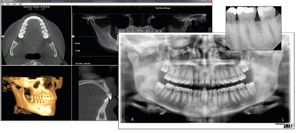

Digital-imaging products, from intraoral sensors to pans and 3D Cone Beam, enhance the patient experience. A digitalimaging system is an educational experience for the patient. Due to the size and clarity of the images in the computer screen, patients can more readily comprehend their conditions, and better evaluate the dentist's recommendations. Digital X-rays and scans build communication and trust between the patient and the doctor, resulting in increased case acceptance.

Besides happy patients, digital equipment from Gendex increases profitability for the practice. Dr. Terry Myers, who has incorporated both 2-D intraoral and 3-D radiographic imaging (Gendex GXCB-500™) into his practice notes that investments in innovative technology are imperative to dentists who want to remain profitable. Dr. Myers notes, "Technology has changed my business. In the recent tough financial times, it is important to keep investing in your practice. The addition of digital technology will allow dentists to better serve their existing patients, attract more patients, and be equipped to make better diagnoses for all."